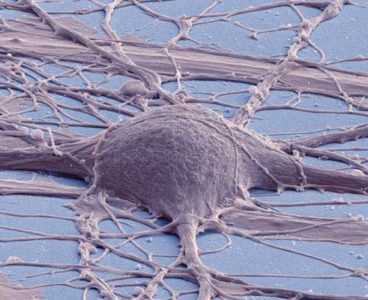

Created Line of Spinal Cord Neural Stem Cells Shows Diverse Promise

Researchers at University of California San Diego School of Medicine report that they have successfully created spinal cord neural stem cells (NSCs) from human pluripotent stem cells (hPSCs) that differentiate into a diverse population of cells capable of dispersing throughout the spinal cord and can be maintained for long periods of time. The achievement, described…